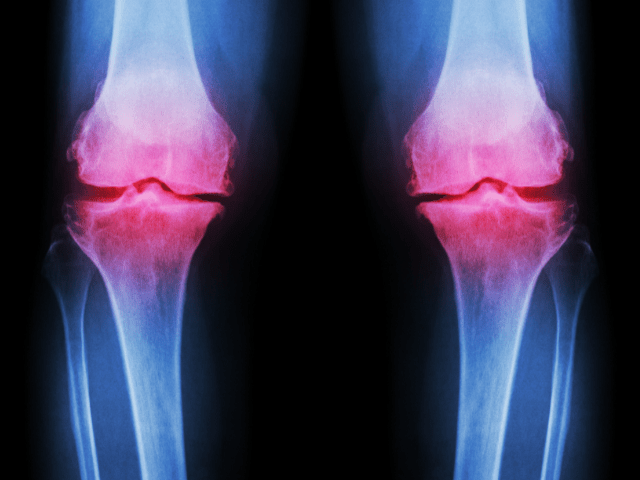

O脚とは、膝が内側に寄っている状態を指します。この状態になると、脚に負担がかかりやすく、健康に悪影響を及ぼす可能性があります。

O脚は、膝や足首、足の裏に負担がかかるため、関節痛や腰痛、疲れやすさなどが生じることがあります。また、歩行時のバランスが崩れたり、スポーツなどのパフォーマンスにも影響を与えることがあります。

O脚による影響は、年齢や症状の程度によって異なりますが、重篤な場合には、手術が必要になることもあります。